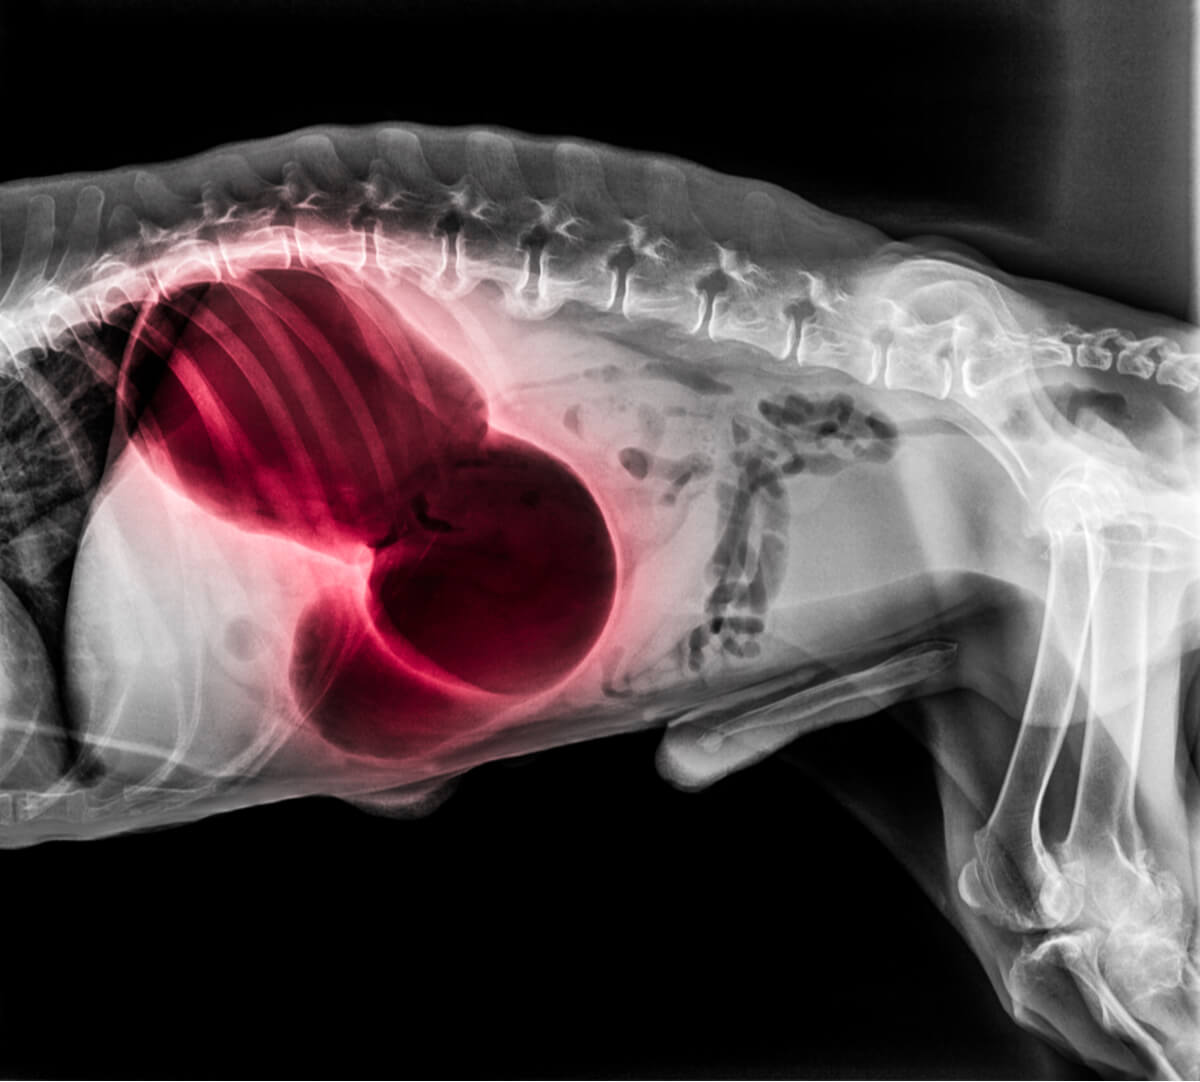

4. Les cancers du tractus gastro-intestinal

Malheureusement, les chiens ne sont pas non plus à l’abri du cancer. Toutefois, cet événement clinique est très rare : le cancer de l’estomac représente moins de 1 % des néoplasmes malins chez le chien. Lorsque cette pathologie aparaît, elle touche généralement les chiens âgés entre 6 et 9 ans.

Les chiens atteints d’un cancer du tractus gastro-intestinal peuvent présenter des selles sanglantes, des difficultés à déféquer, des douleurs abdominales et même une masse tumorale palpable au toucher. Selon le type de tumeur, le pronostic peut aller d’excellent à mortel.